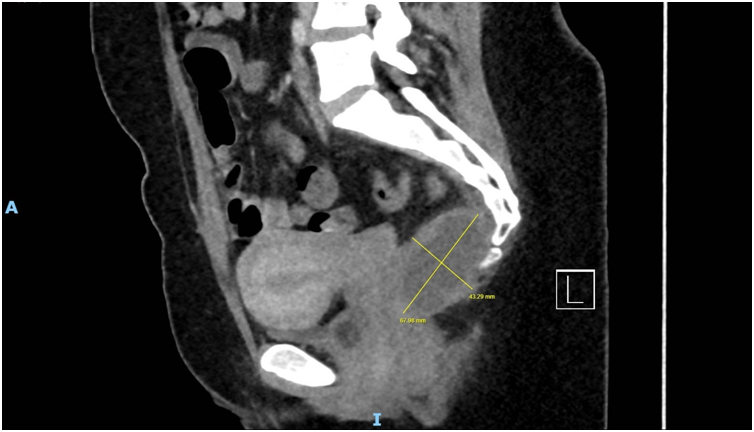

Imaging via MRI and CT demonstrated a complex, encapsulated lesion with peripheral enhancement and restricted diffusion. Multidisciplinary evaluation suggested a congenital epidermoid or duplication cyst. Given the absence of malignancy and surgical complexity, a conservative management strategy was adopted.

Figure 1: Figure 1 Duplication cyst 2025 MRI sagittal plane

Figure 2: Figure 2 Duplication cyst 2025 MRI sagittal plane

Figure 3: Figure 3 Duplication cyst 2020 Coronal plane

Figure 4: Figure 4 Duplication cyst 2020 sagittal plane

Figure 5: Figure 5 Duplication cyst axial 2020 plane post cystic aspiration

Figure 6: Figure 6 Duplication cyst 2025 sagittal plane

Figure 7: Figure 7 Duplication cyst 2025 MRI axial plane

Figure 8: Figure 8 Duplication cyst 2020 axial plane